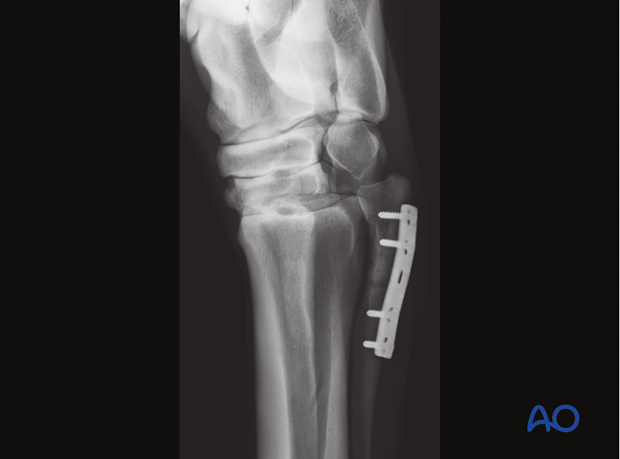

Proximal Fracture of MC IV - 6-hole 3.5 one-third Tubular Plate

A 3.5 mm (narrow) DCP, LC-DCP or LCP, third-tubular plate or reconstruction plate (LCP/DCP) is appropriate in most cases.

Usually a 5-hole plate can be used. The distal part of the splint bone becomes very thin, which prevents the use of a longer plate in most horses.

Completed fixation